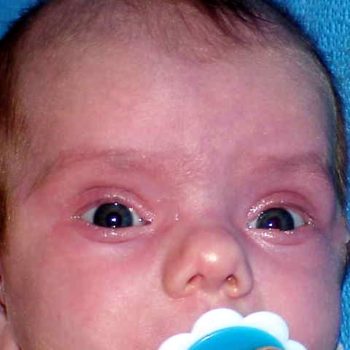

Note what signs you see.

I (L. Yevtushok, M.D.) see a palm with a transverse distal flexion crease with an exit point between fingers 2-3. Some dysmorphologists call such crease, “jockey stick” – like, and consider such pattern as more frequent among children with Fetal Alcohol Spectrum Disorders (FASD). I also see a thenar flexion crease. There is no evidence of a proximal transverse flexion crease. There is considerable variability of the patterns by the mentioned creases. For more on this subject, see “Dermatoglyphics”.

PERSPECTIVE: Please see the rest of the image gallery and comments.